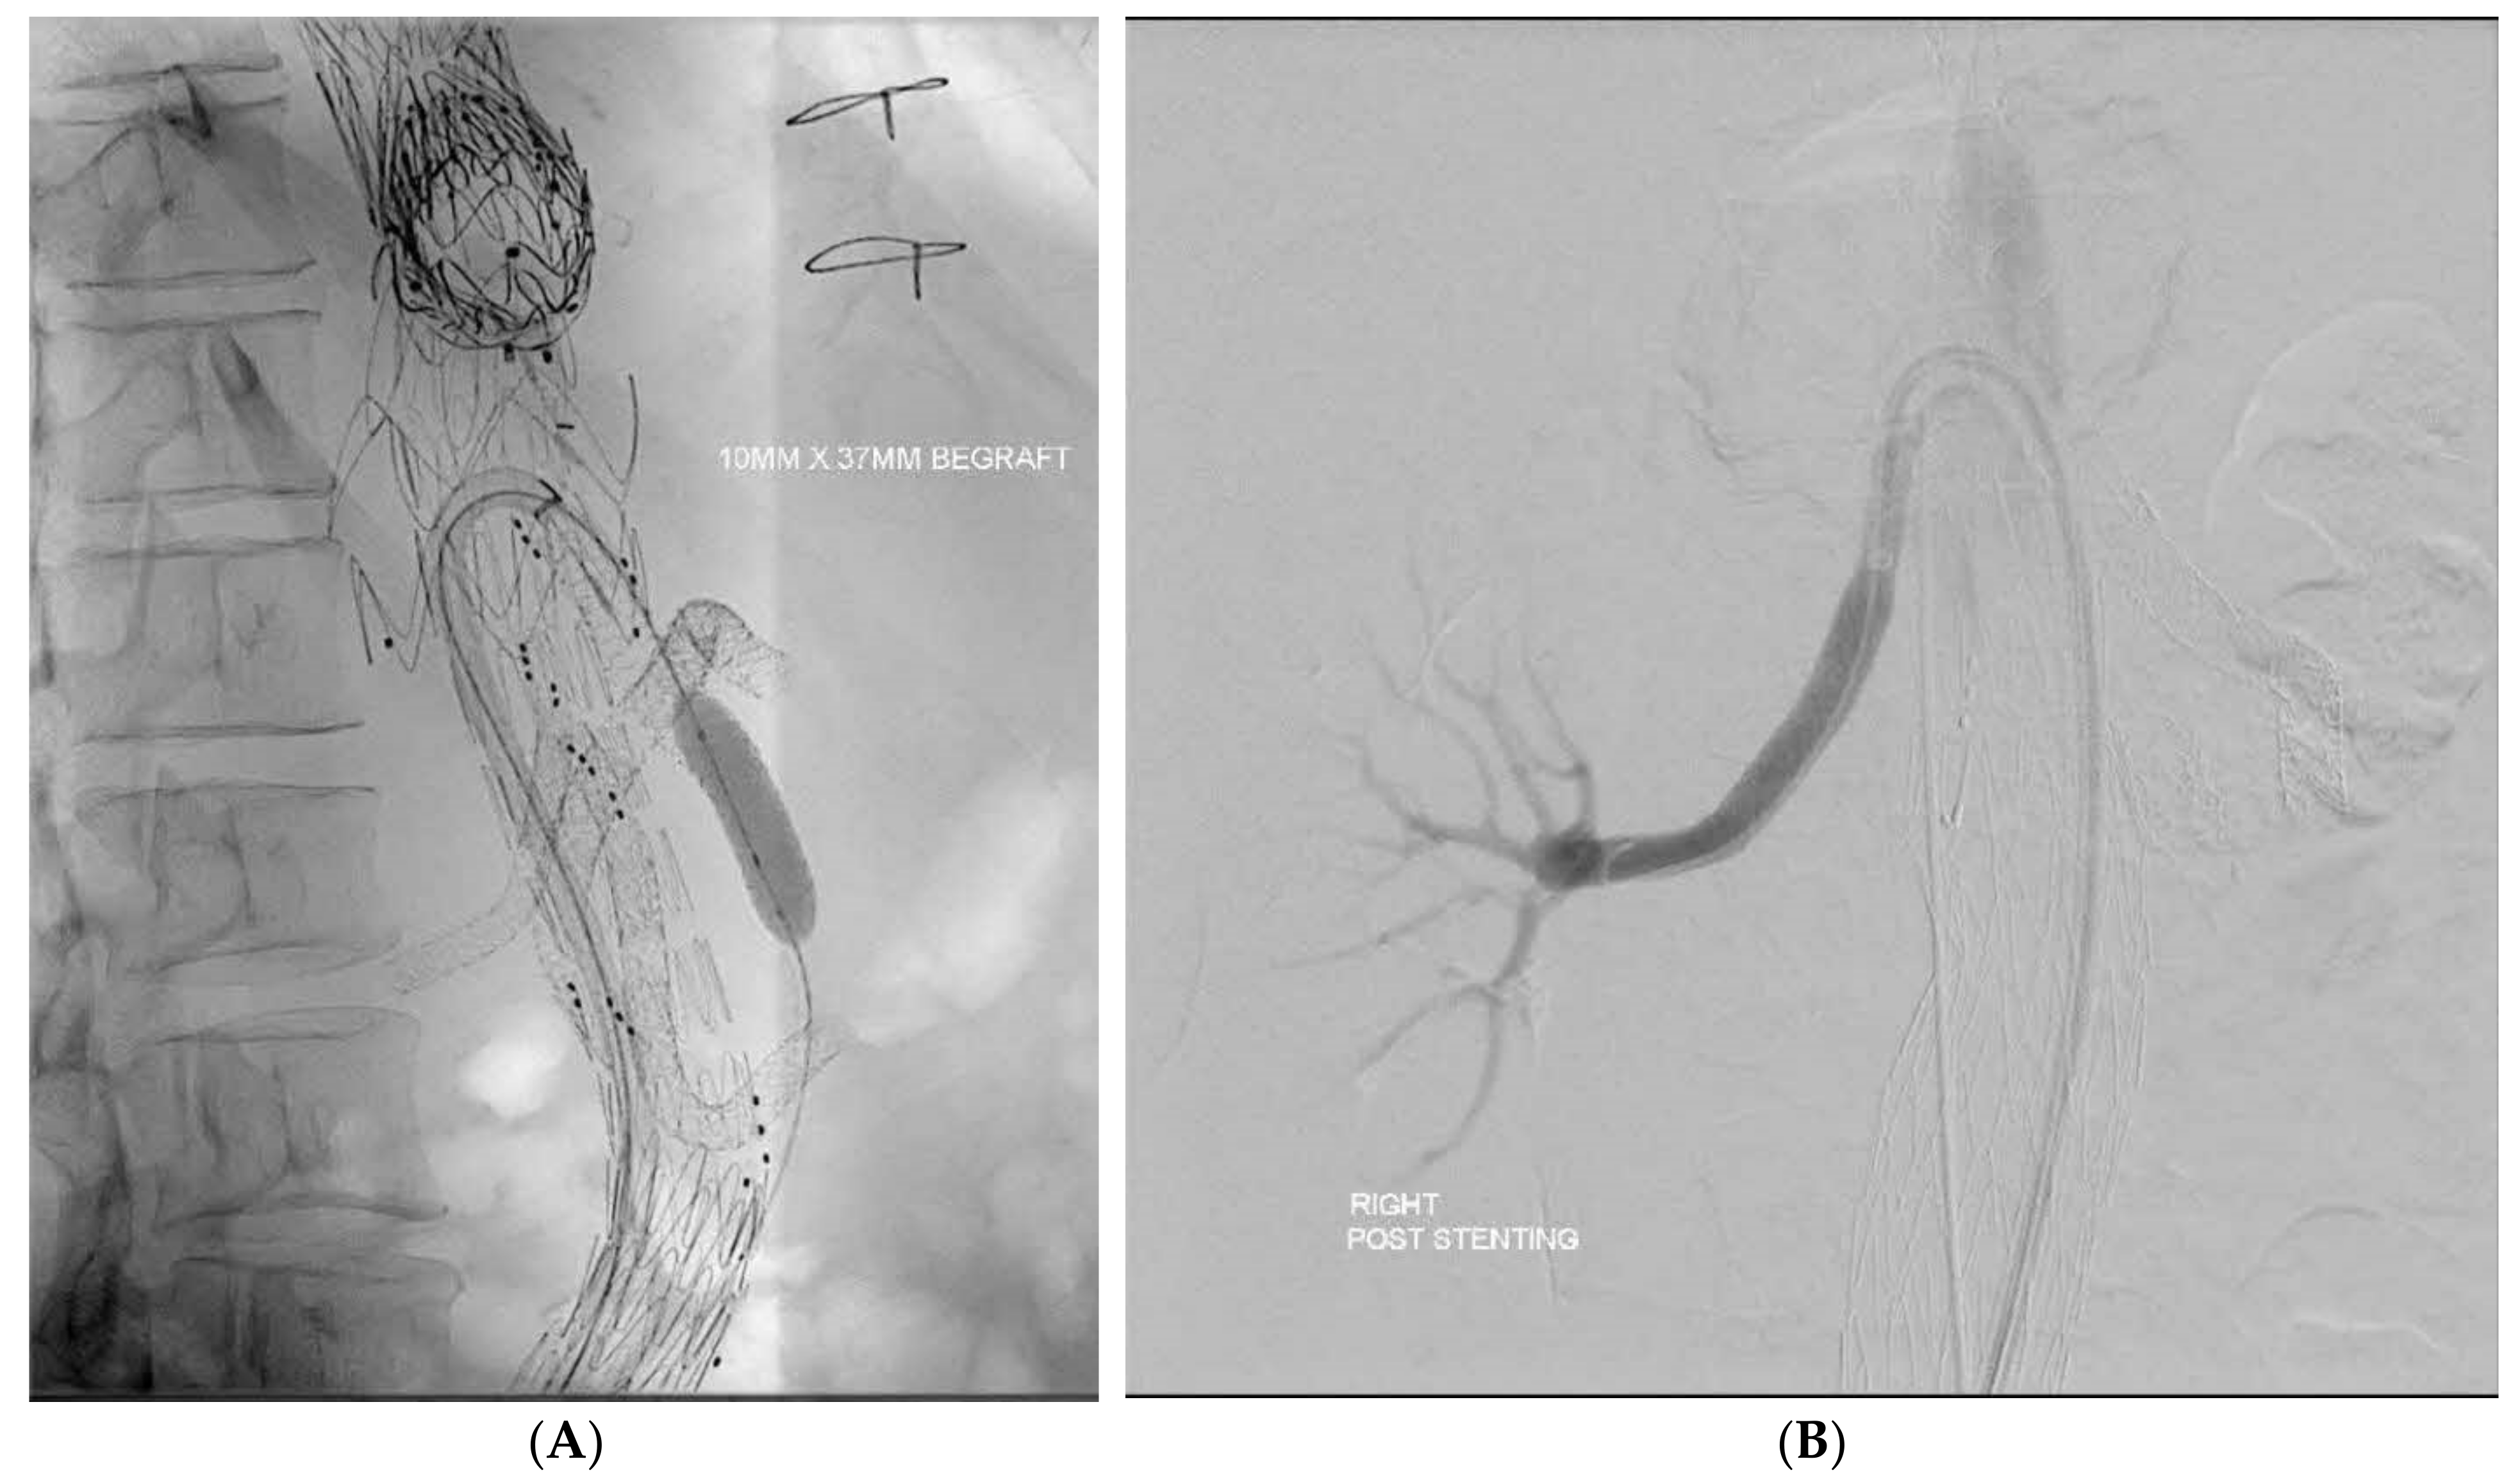

Branch occlusions | All > 1 year incidental on surveillance 4 renal—3 patients, 1 bilateral underwent thrombolysis, 2 unilateral—treated conservatively |

Aortic limb occlusion | 2 iliac limbs, required thrombolysis and relining |